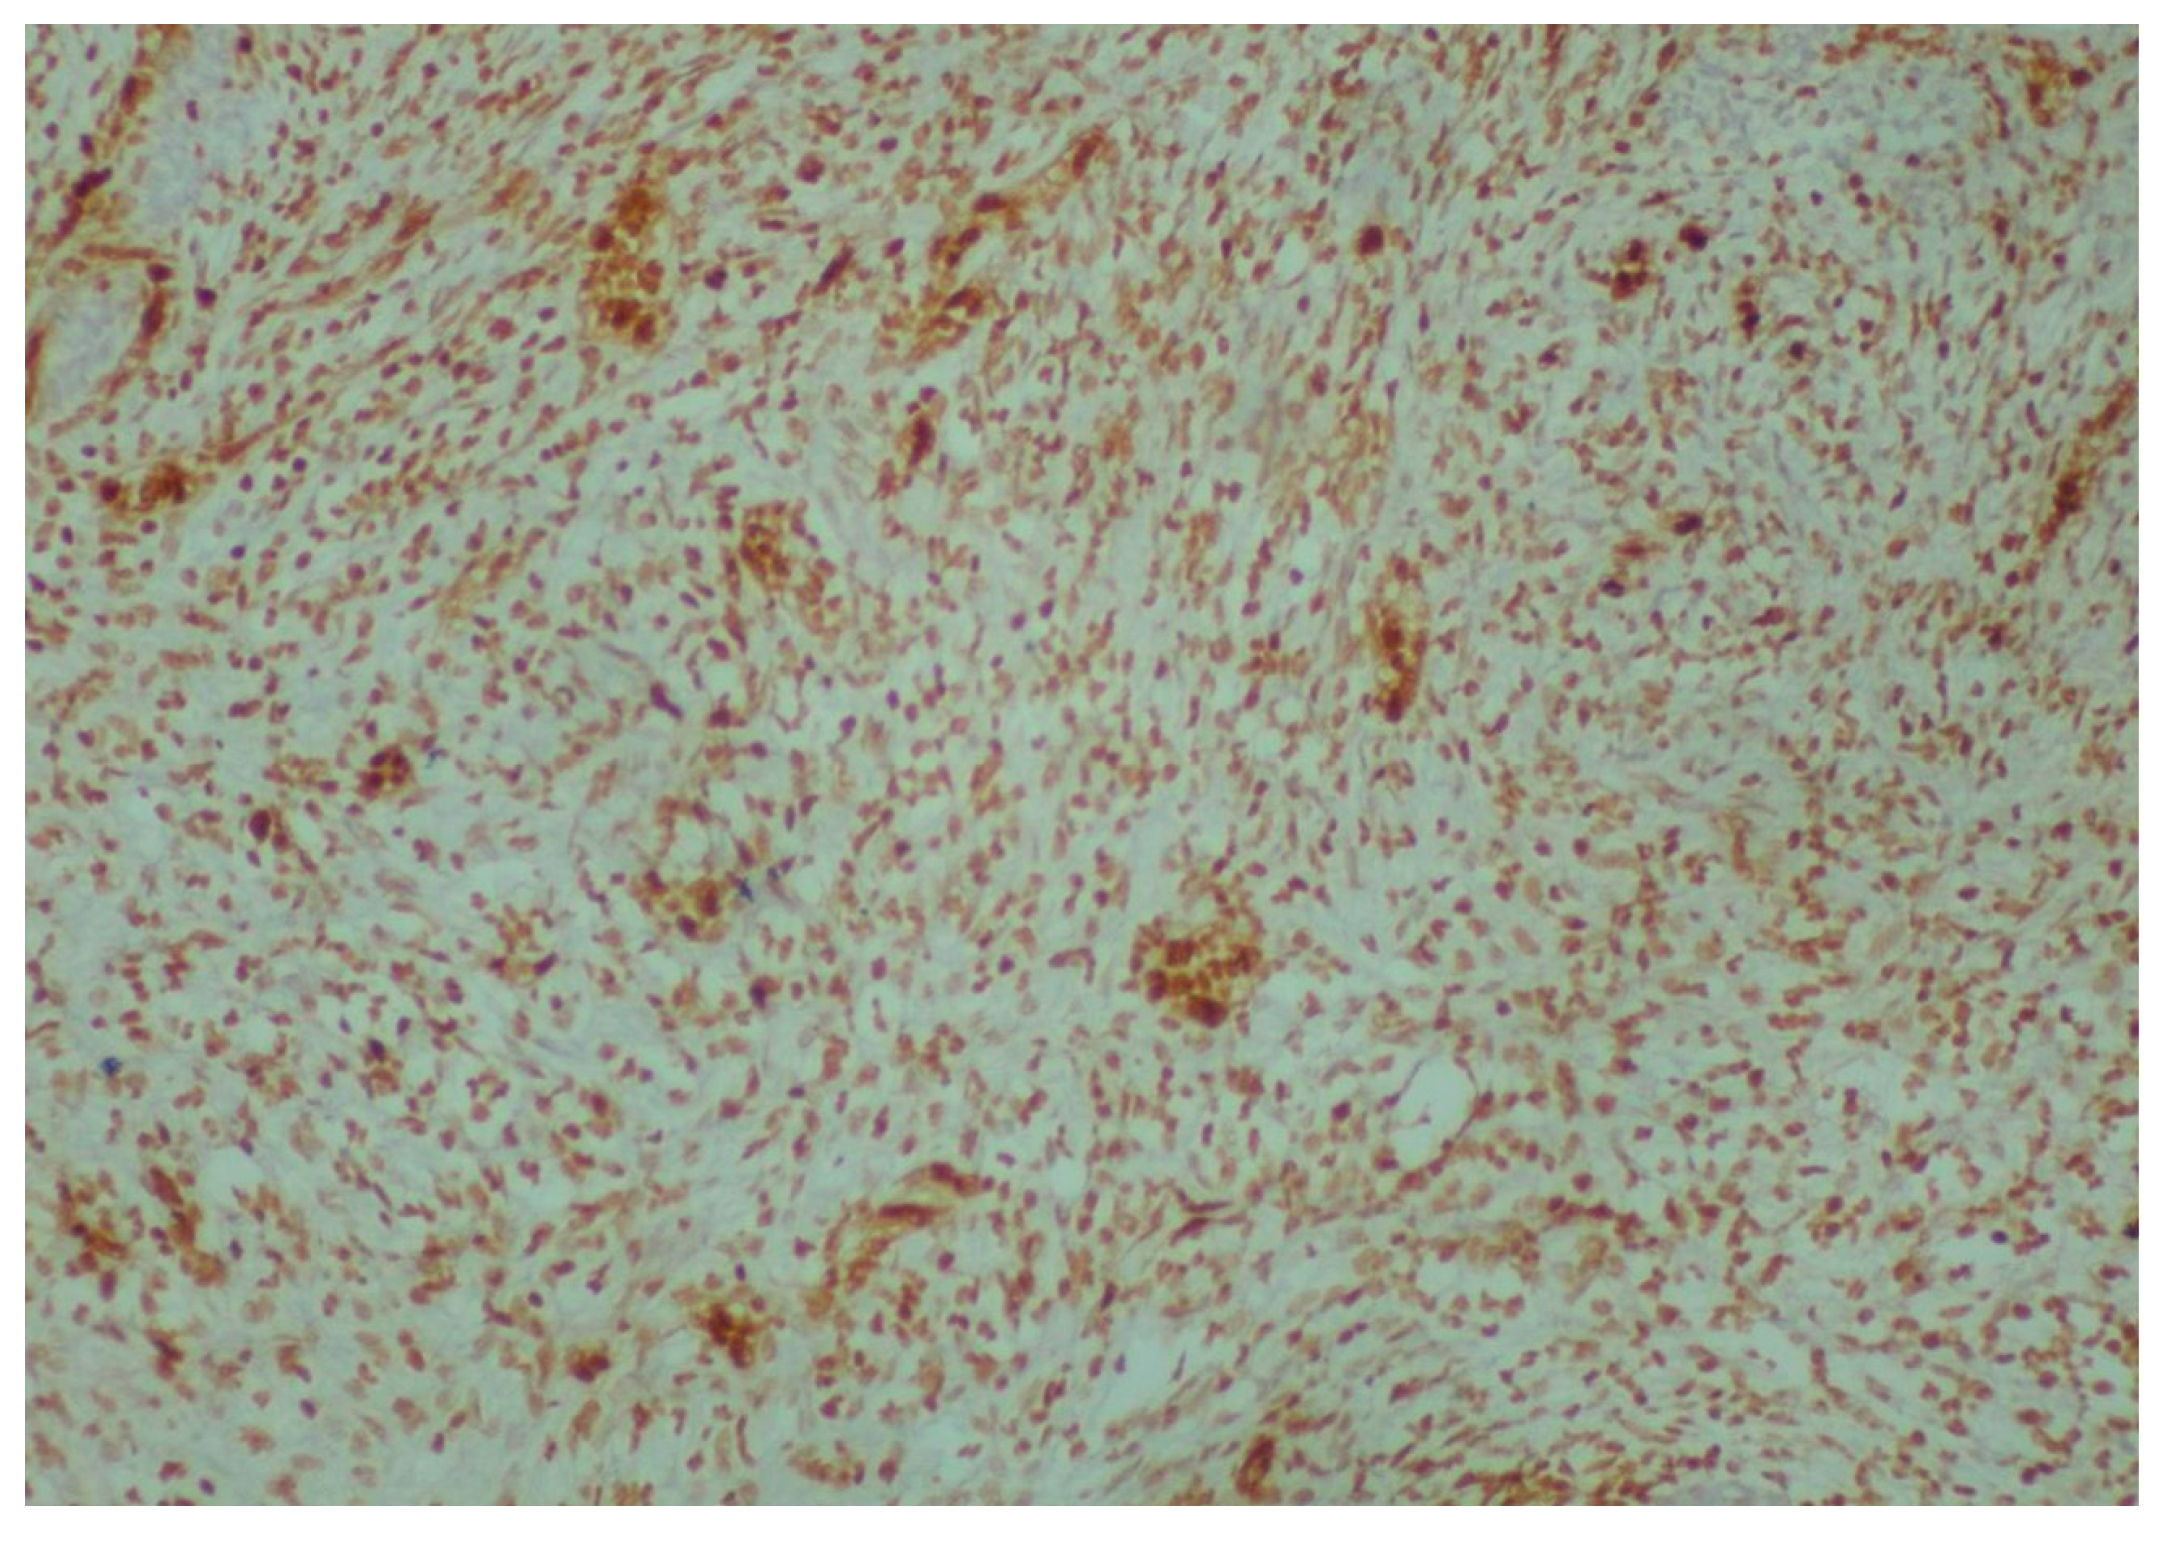

2. Case Presentation